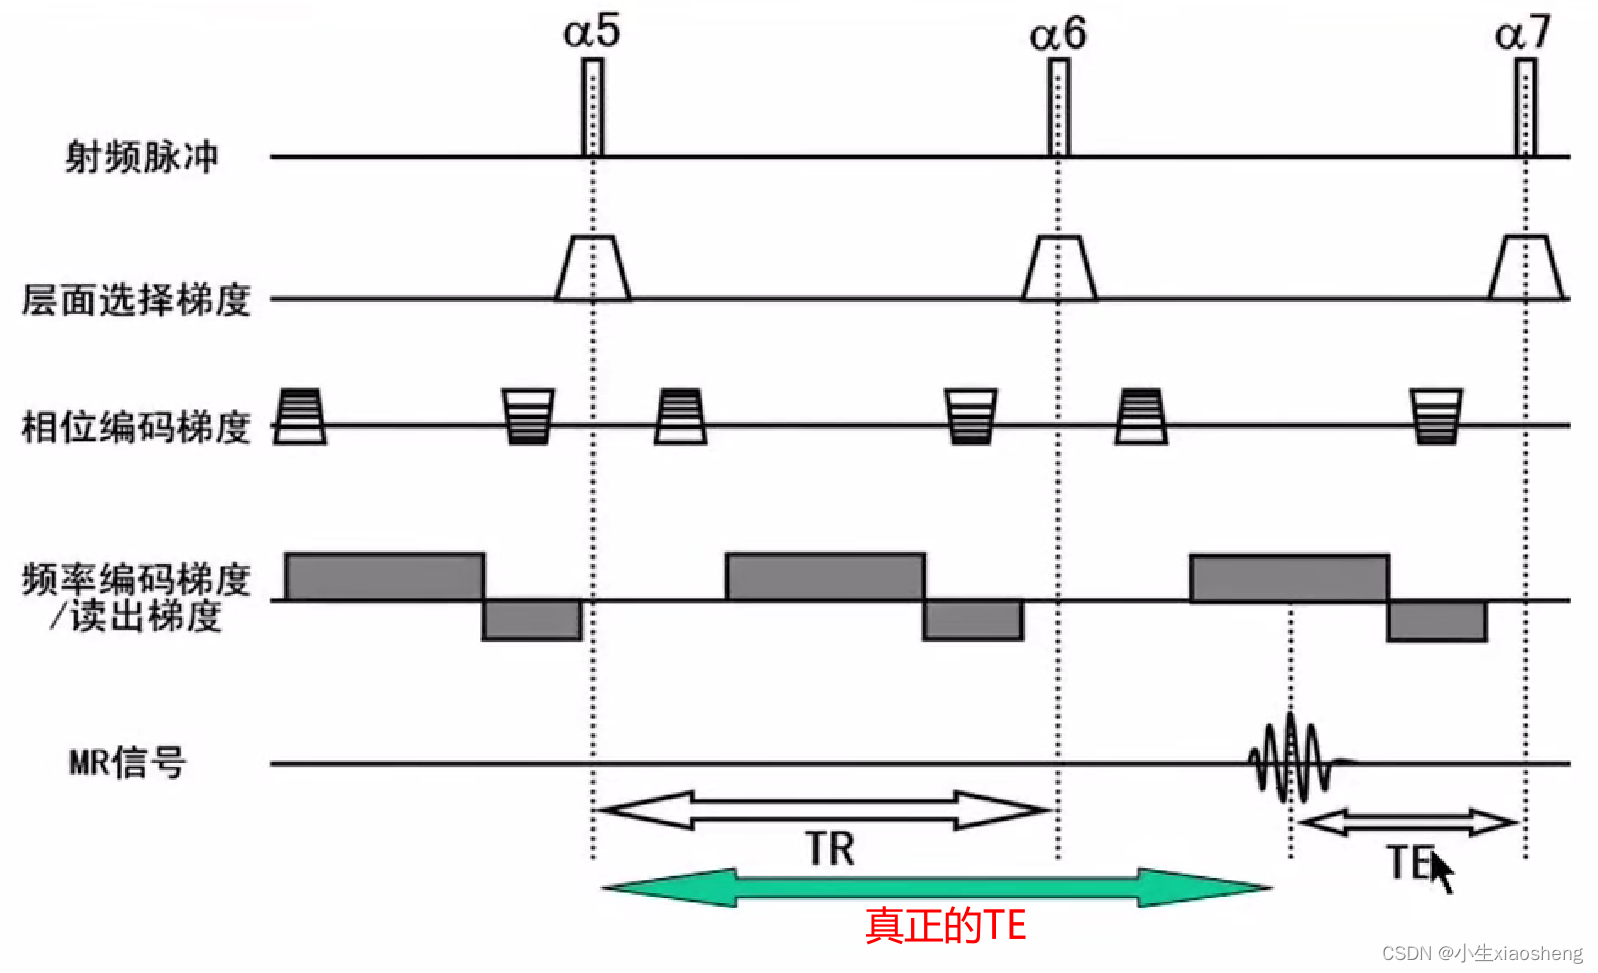

TR代表重复时间(repetition time),是指脉冲序列执行所需的时间

TE代表回波时间(echo time),是指产生宏观横向磁化矢量的脉冲中点到回波中点的时间间隔

相位编码梯度和频率编码梯度/读出梯度:主要功能就是在脉冲消失之后采集数据,能横向量编码很快衰减。